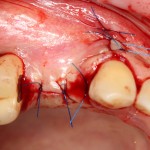

И вроде бы, все неплохо, но когда мы скелетируем костную ткань, то видим следующее:

Можно ли поставить импланты? Теоретически, если использовать импланты диаметром 3,0 мм — вполне возможно. Но как это будет потом выглядеть? Большие коронки на тоненьких имплантах с тонкой десной? А если эти зубы еще попадают в эстетически значимую зону и видны при улыбке? А если это еще и девушка, которая собирается замуж? И вот тут встает вопрос о размерах и позиционировании имплантов, который тянет за собой вопрос об остеопластике.